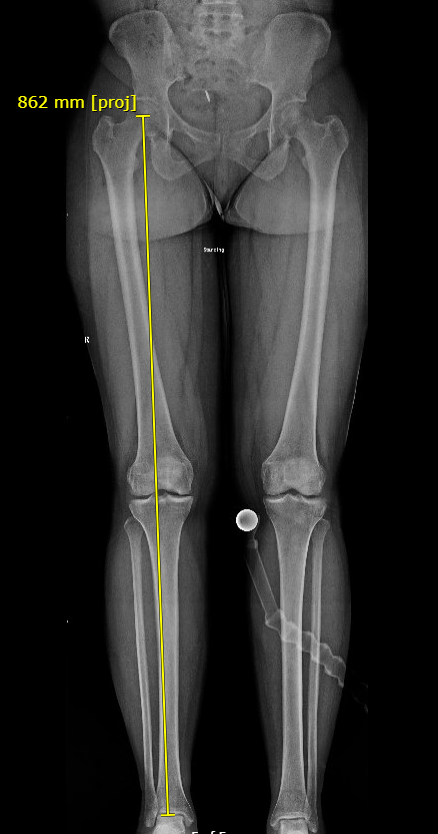

Mechanical Axis Deviation

- distance from center of knee to MA in mm